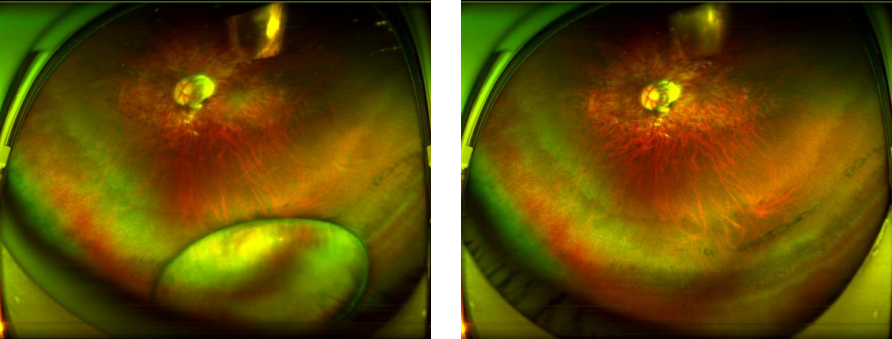

出院后患者自觉视力恢复不明显,遂至华厦眼科医院赵铁英院长门诊求治,此时伤后两个多月眼底积血部分吸收及下沉,可见明显的外伤性黄斑裂孔、及右眼视网膜脉络膜挫伤瘢痕,视力已下降到 0.25,虽然黄斑裂孔的直径仅600多微米,但已是这类疾病中的比较大的裂孔了,而且对视力影响巨大!这对自90年代末在广州中山眼科中心攻读博士期间就开始研究黄斑裂孔治疗的赵铁英院长来说治疗方案还是非常明确的,早在2015年她就在《中华眼科杂志》上发表过一篇有关外伤性黄斑裂孔治疗的文章。

图:小尼手术前后追踪扫描图

目前眼底显微外科微创设备器械不断升级,27G微创玻璃体视网膜器械就是深圳华厦眼科医院在深圳地区最早引进使用的。在经过关键步骤需屏住呼吸的精稳手术操作后,赵铁英院长将小尼的“视网膜心脏穿孔”成功修补封闭,术后两周,小尼的右眼视力已经提高到0.5。